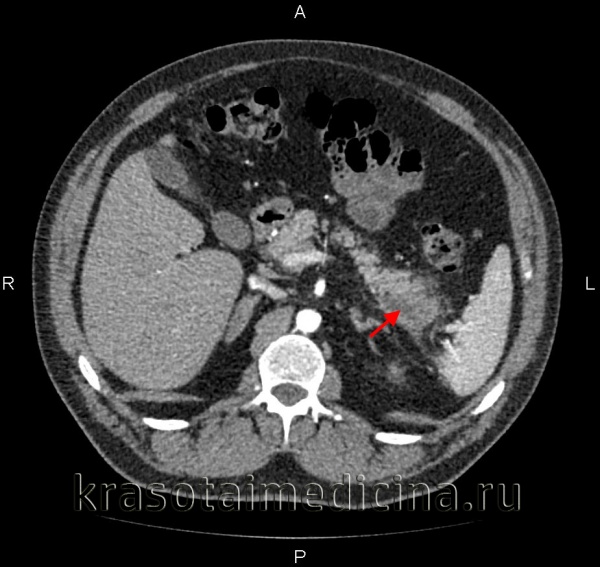

КТ органов брюшной полости. Множественные кальцинаты в области хвоста и тела поджелудочной железы (последствия множественных острых эпизодов панкреатита)

КТ органов брюшной полости. Панкреатит (в области хвоста поджелудочной железы) с наличием отека ее паренхимы, жидкостного содержимого вблизи ее края, на фоне утолщение фасции Героты слева